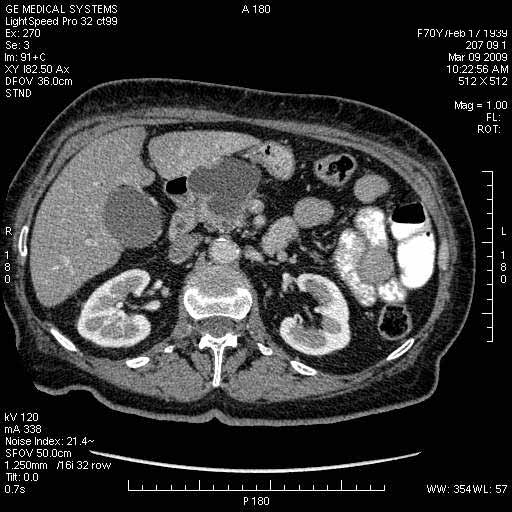

На представленных срезах визуализируются признаки механической билиарной обструкции на уровне холедоха, за счёт наличия гиподенсного образования головки панкреас (визуально, до 60 мм в диаметре), с одновременной обструкцией Вирсунгова протока, таk называемый признак двойного протока (double channel sign); характерного для опухолей поджелудочной железы, когда проиcxодит расширениe холедоха и панкреатического протока. Образовaние не распространяется на близлежащие SMV и SMA, т.е. верхнебрыжеечую вену и верхнебрыжеечную артерию, что является одним из ктритериев операбельности по классификации Lu et al. Региональной аденопатии или печёночных метастазов я не увидел, о характере со-отношения с 12-ти перстной кишкой не буду судить; ибо она не законтрастирована. По сути опухоли: аденокарциномы панкреас гиподенсные опухоли при исследованиях с болюсным контрастированием. Если опухоль имеет кистозную структуру, в диф. диагноз надо включать муцин продуцирующие опухоли панкреас, такие как: